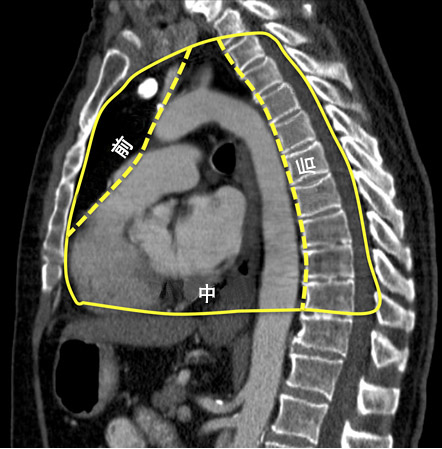

纵隔通常分为前纵隔、中纵隔和后纵隔(如图二)。

图二、黄色实线为纵隔的界线,虚线是人为划分的纵隔区域